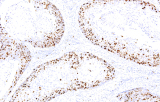

Anticorpos primários contra recetor de estrogénio (ER), recetor de progesterona (PR), HER2 e Ki-67 continuam a ser a pedra angular da classificação e decisões terapêuticas no cancro da mama. Estes anticorpos estão validados clinicamente e marcados CE/IVD para garantir deteção fiável e reproduzível de biomarcadores – crucial para orientar terapia hormonal e estratégias de tratamento direcionado.